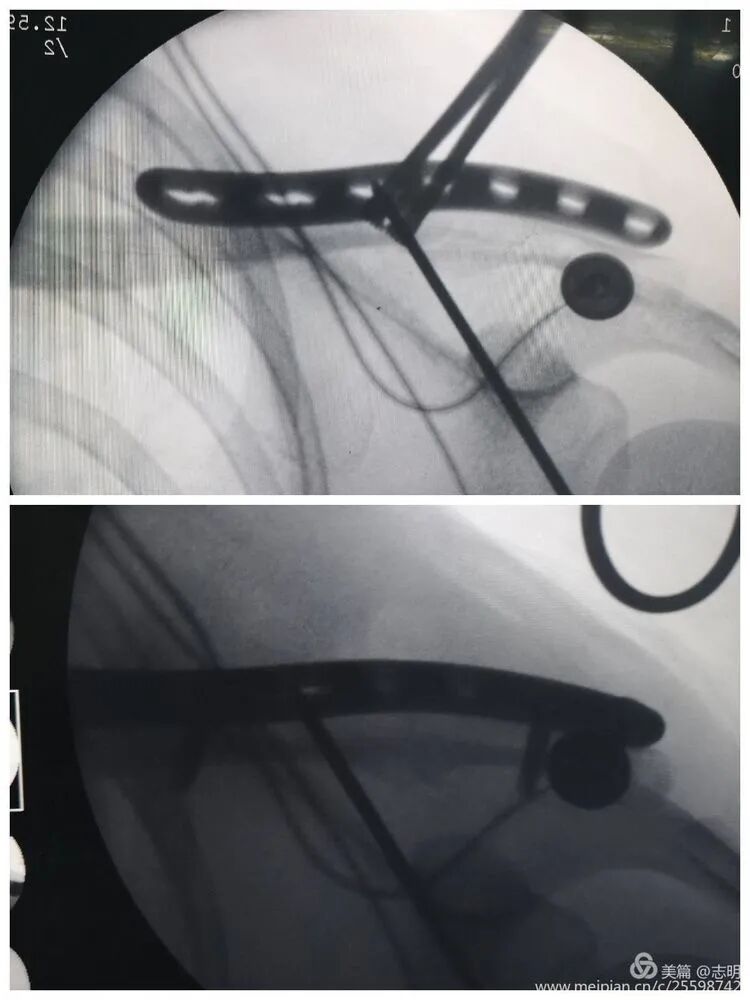

- Plate Passage: Once reduction is satisfactory and temporarily stabilized, pass the pre-contoured locking plate through the subcutaneous tunnel. Use specialized plate manipulators to guide the plate and ensure it lies flush against the clavicle.

(Fluoroscopy confirming plate position).(Another fluoroscopy view of plate position).

- Plate Passage: Once the fracture reduction is deemed satisfactory and secured with temporary fixation, the pre-contoured locking plate is carefully passed through the previously created subcutaneous tunnel. Specialized plate manipulators and guides are used to ensure the plate lies snugly and flush against the superior or anterosuperior cortical surface of the clavicle.

(Image depicting the insertion of a plate through a small incision).(Fluoroscopic image confirming proper plate positioning).(Another fluoroscopic view illustrating the plate's final position).